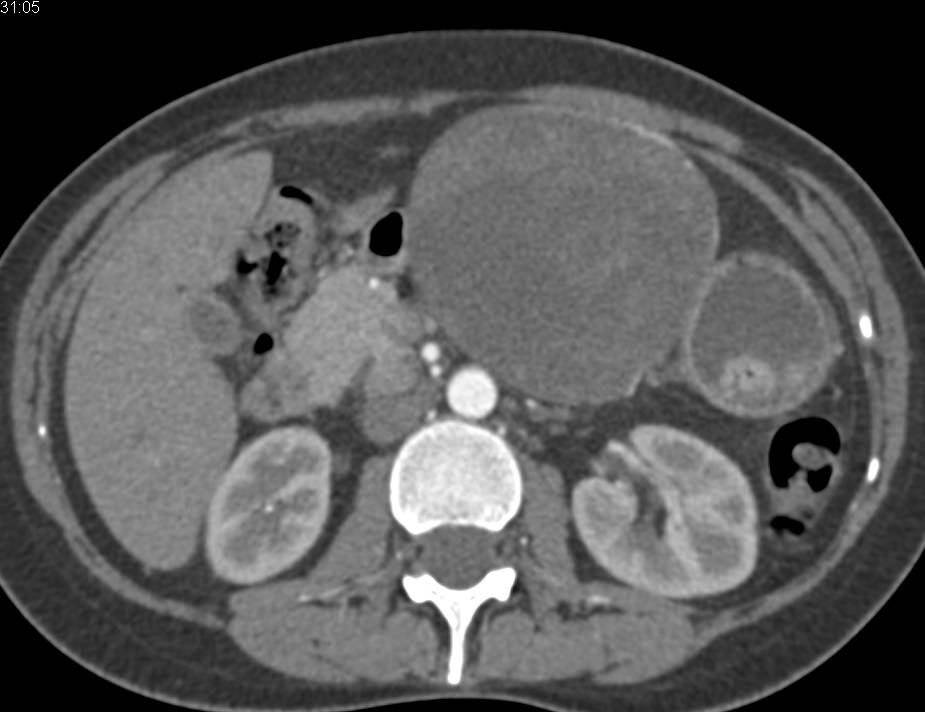

Gastric Cancer with Liver Metastases and Pericardial Effusion